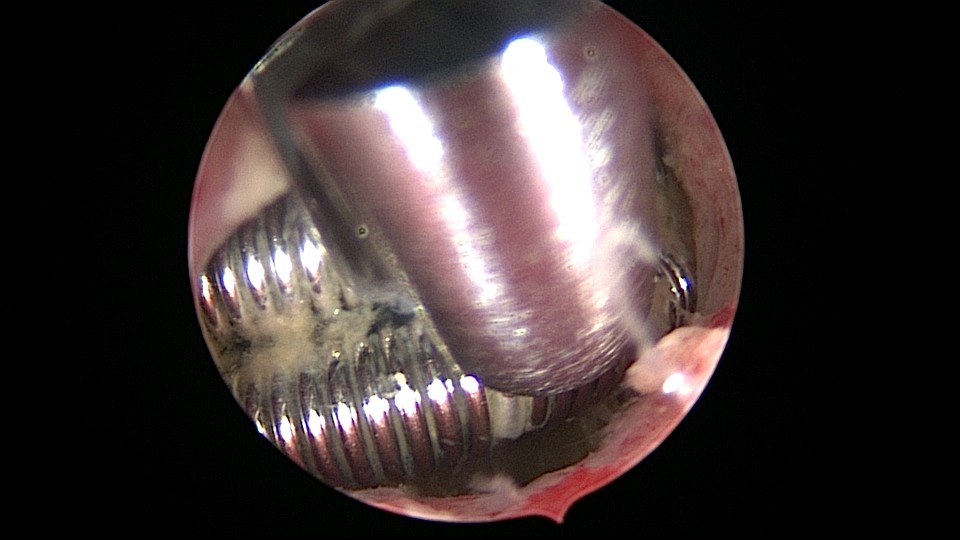

患者58岁,G2P1,顺产1次。安环35年,绝经15年,5年前在外院取环失败。术前B超提示子宫后位,O型环嵌顿,环顶端距宫底0.7cm。宫腔镜术中见阴道口狭小,无法置入窥阴器,宫颈外口狭窄,镜鞘缓慢扩大。宫颈内口粘连,左侧似有一小孔,异物钳扩大小孔,见较多浓稠黄色液体流出,冲洗干净后推进宫腔镜,见2个O型节育环,上面的环取出顺利,下面那个环与宫腔侧壁嵌顿,2次牵拉滑脱,第三次一张一驰松动节育环,再缓慢拉出,宫底见2道环压痕。